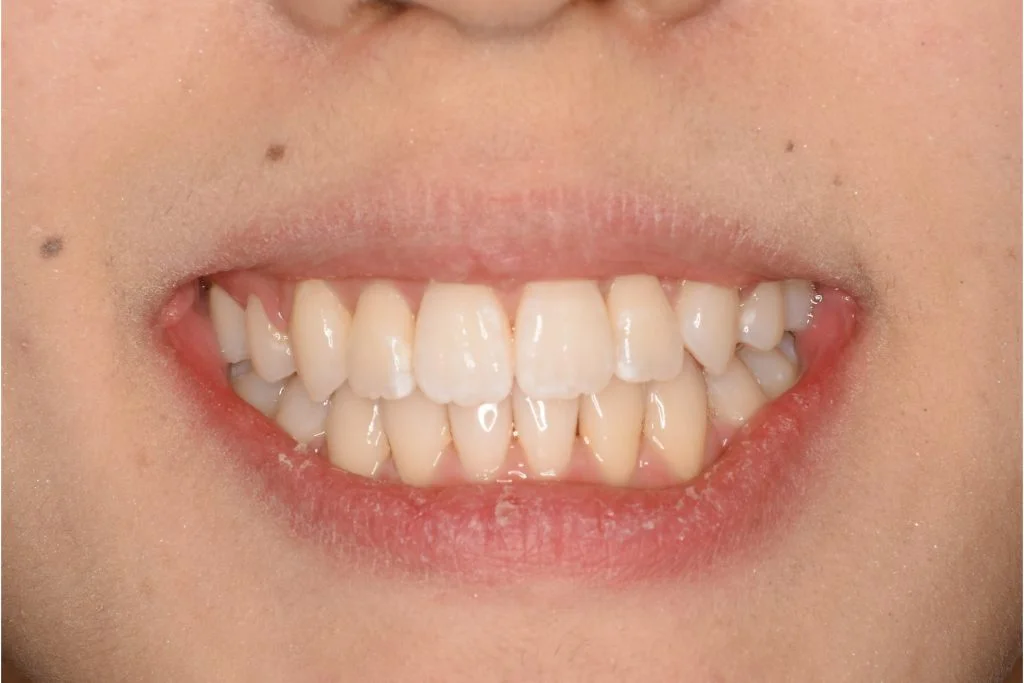

• 症例1-1治療後

治療後 マウスピース矯正のみで治療

治療後 とても綺麗な笑顔になりました

患者さんの感想 他ではワイヤー矯正でしか治療できないと言われていたので、最初はマウスピース矯正で本当に治るのかなと少し心配でしたが、治療期間も短く、こんなに綺麗になってお願いして本当によかったです。長年コンプレックスだった歯並びが綺麗になって、以前は自分の口元を見るのが嫌でしたが、口元に自信が持てるようになり、人前で気にせず笑えるようになって人生が変わりました。

費用 抜歯ありのマウスピース矯正:880,000円(税込)